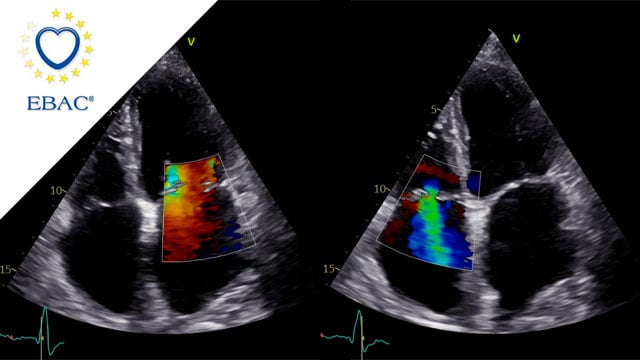

Severe MR in a high-risk patient with a suboptimal anatomy for M-TEER: what other options can we find?

Multimodality imaging reveals fibro-calcific leaflet disease, restricted motion, and a short posterior leaflet, making him a suboptimal candidate for M-TEER and prompting consideration of transcatheter mitral valve replacement. How would you treat?